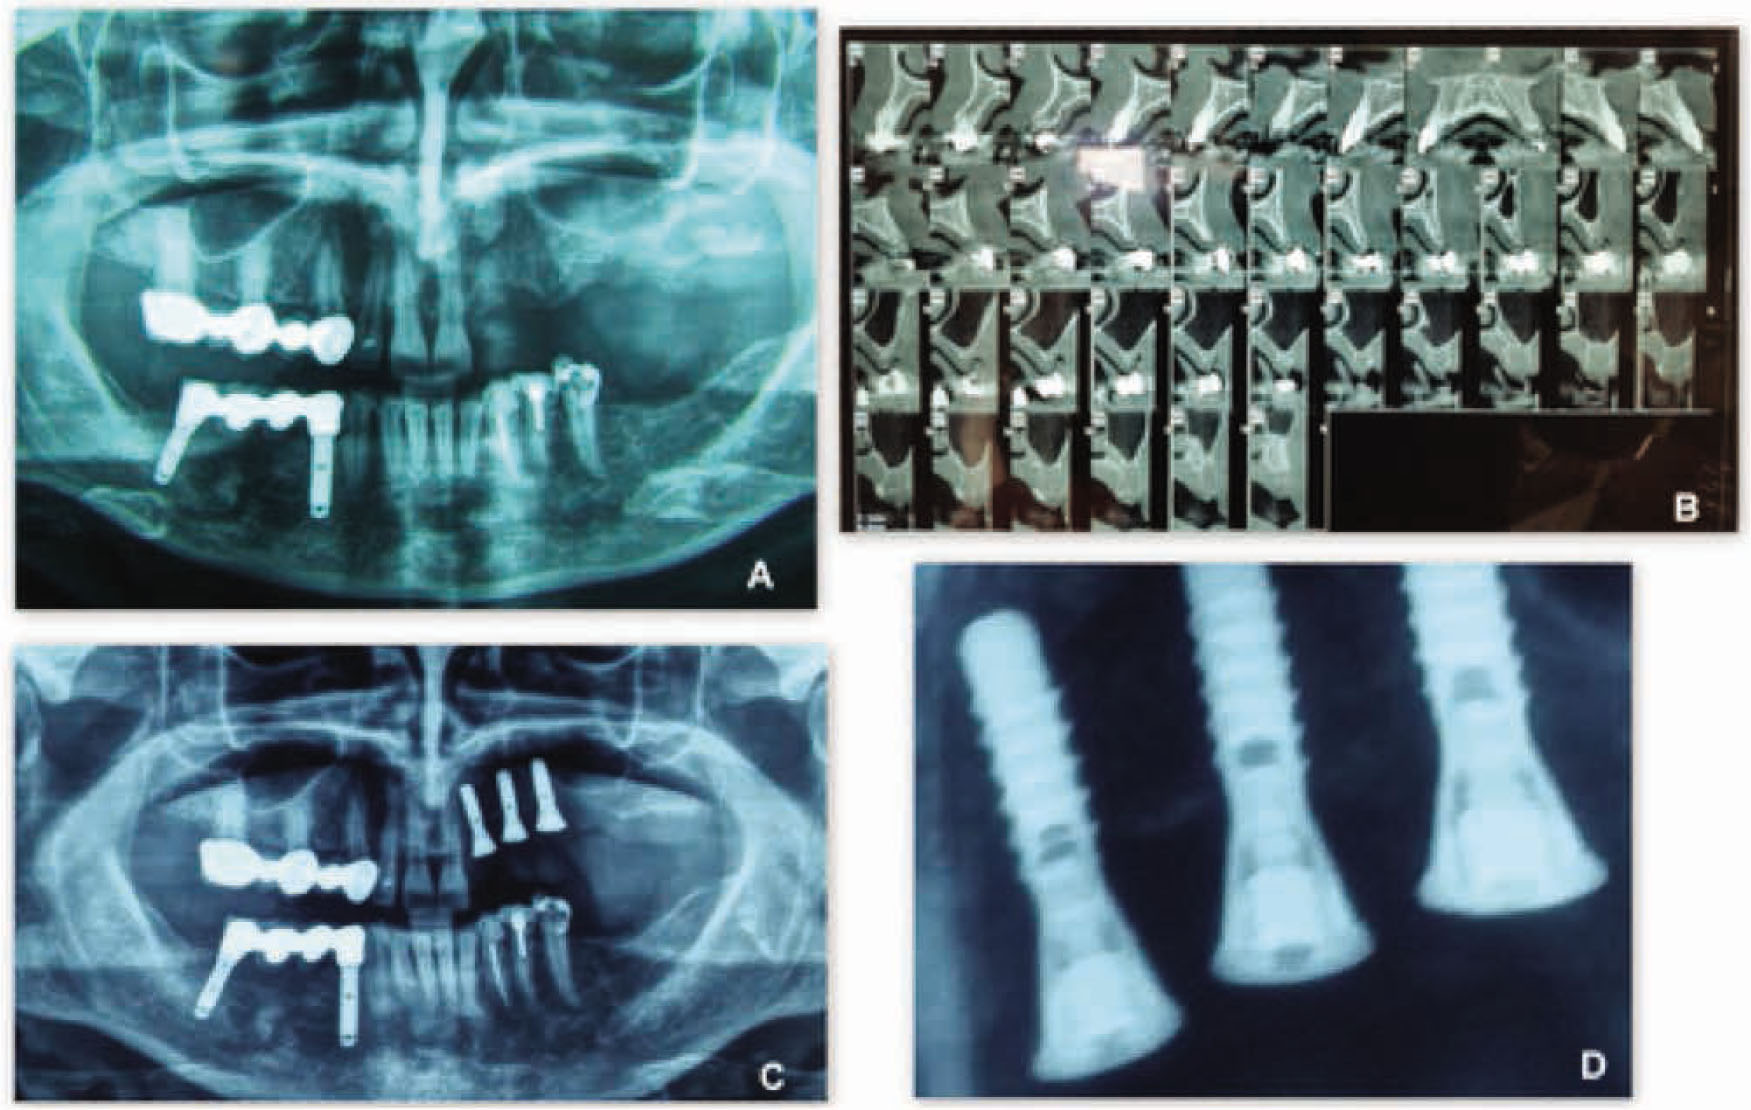

Figure 5 Radiographic views of a patient treated with the new flapless split crest procedure combined with PRF.A: Pre-operative X-Ray Orthopantomography;B: Pre-operative CT-Dentascan;C: Post-operative X-Ray Orthopantomography;D: 6 months post operative detail X-Ray image of the bone level at T3.

Figure 5

Radiographic views of a patient treated with the new flapless split crest procedure combined with PRF.

A: Pre-operative X-Ray Orthopantomography;

B: Pre-operative CT-Dentascan;

C: Post-operative X-Ray Orthopantomography;

D: 6 months post operative detail X-Ray image of the bone level at T3.